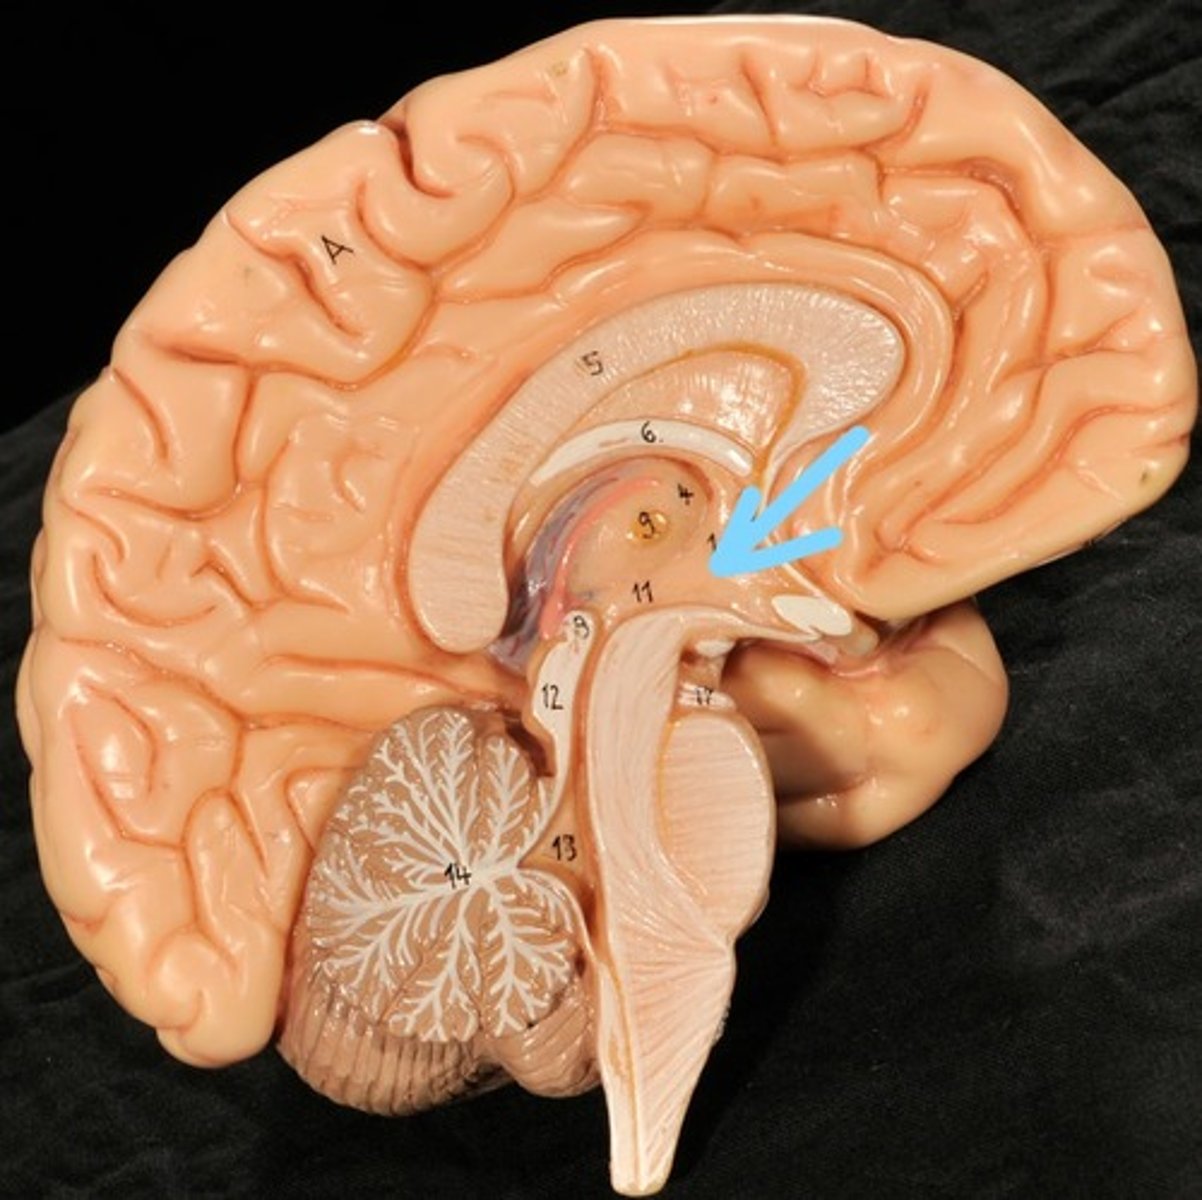

Identify structures of midsagittal brain

Corpus callosum

Diencephalon

thalamus, third ventricle, hypothalamus, epithalamus

Thalamus

Third Ventricle

Hypothalamus

Epithalamus (pink line)

Brain stem

Pons

Medulla oblongata

choroid plexus of third ventricle

produces cerebrospinal fluid

Third ventricle

cerebral aqueduct (midbrain)

midbrain

Fourth ventricle

Central Canal of brain

Takes Cerebrospinal fluid down to the spinal cord

Thalamus